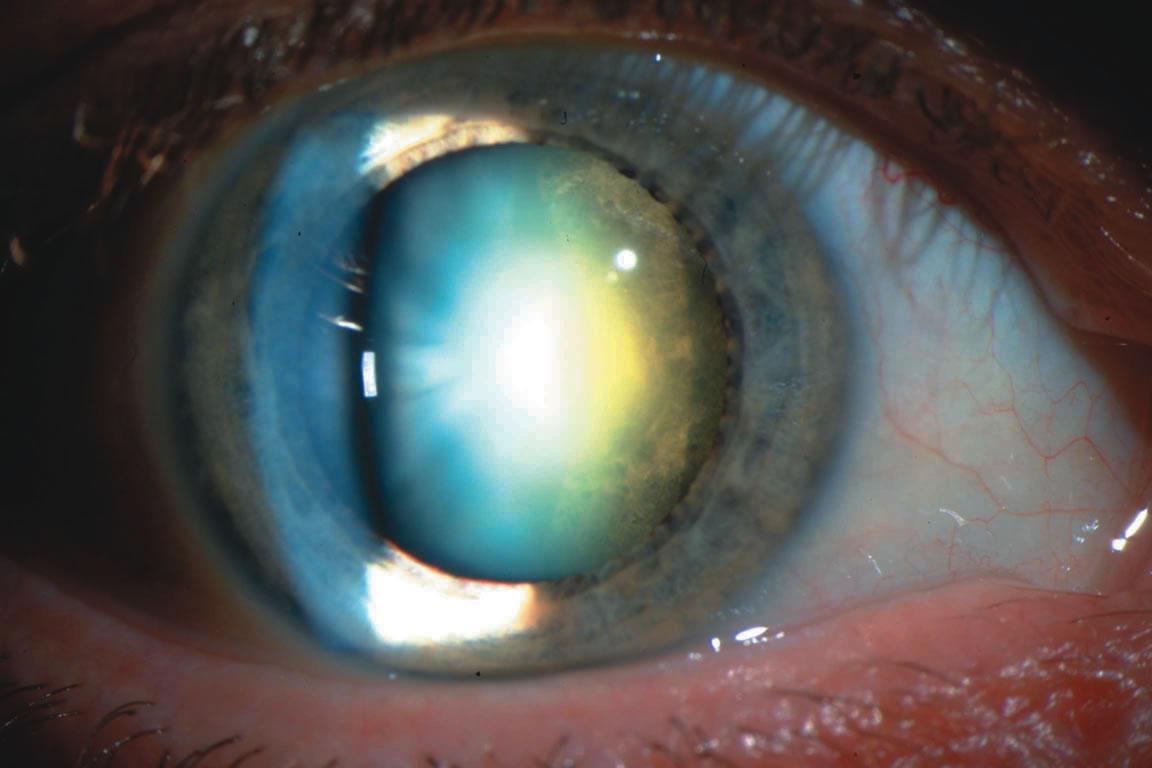

Fig. 3. Posterior subcapsular cataract (PSC) using (A) direct illumination and (B) retroillumination. PSCs usually start centrally and extend toward

the periphery. For this reason, they interfere with visual function, causing

glare disability early.

Fig. 3. Posterior subcapsular cataract (PSC) using (A) direct illumination and (B) retroillumination. PSCs usually start centrally and extend toward

the periphery. For this reason, they interfere with visual function, causing

glare disability early.

beams. Retroillumination uses the light reflected from the fundus to highlight

opacities. This is very useful in examining cortical and posterior subcapsular

cataracts (Figs. 1, 3, 7, and 8). However, some cortical water clefts and early posterior subcapsular

opacities may not be easily seen with retroillumination if they are

not dense enough to cast shadows or only refract the retroilluminate

light; these can be best seen with the broad beam. Using retroillumination